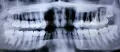

Необходимо маму очно осмотреть и посмотреть рентген-снимки. Я немного не понимаю какой диагноз был и что Вы подразумеваете под выражением пломбировали (каналы или устанавливали пломбу).